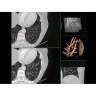

КТ аппарат GE Optima CT520

Современный КТ-аппарат с высокой скоростью сканирования и точной визуализацией. Обеспечивает детализированные снимки для надежной диагностики. Экономичное энергопотребление и удобное управление повышают эффективность работы. Отличный выбор для медицинских учреждений любого уровня.

Современный КТ аппарат GE Optima CT520 – это инновационное оборудование для точной и быстрой диагностики. Он сочетает в себе передовые технологии, надежность и удобство использования, что делает его востребованным в медицинских учреждениях различного профиля.

• Высокое качество изображения благодаря усовершенствованной системе реконструкции данных.

• Сниженная лучевая нагрузка на пациента без потери информативности снимков.

• Широкая область применения: от неврологии до кардиологии и онкологии.